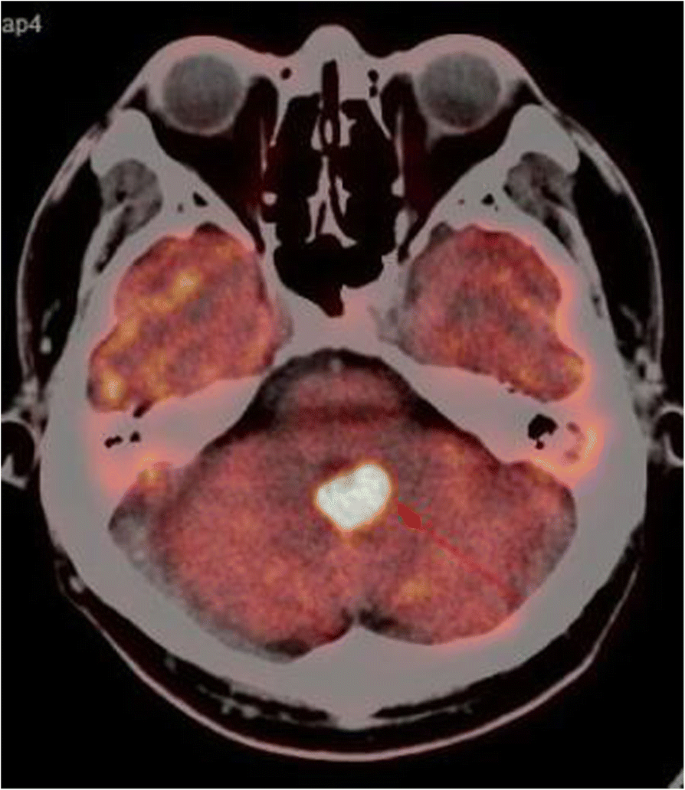

A typical case: a 38-year-old right-handed male was hospitalized mainly due to progressive left limb fatigue for more than 3 months and aggravated nearly 1 week. Physical examination showed a poor coordinate movement of the left limbs. Enhanced MRI and magnetic resonance spectroscopy imaging indicated multiple intracranial neoplastic lesions, probably lymphoma (Figs. 1, 2, and 3). PETCT scan showed a high-level metabolism in the lesion areas (Figs. 4 and 5). MRI was performed to locate the lesions after preoperative installation of the Leksell headgear (Fig. 6). Preoperative surgical plan was conducted at the BrainLab workstation. Multi-image fusion-guided stereotactic surgery was performed for intracranial lesion biopsy. Multi-image fusion and three-dimensional reconstruction showed the relationship between lesions and fiber bundles as well as intracranial vessels (Fig. 7). Based on the biopsy target and the path, the biopsy needle was placed into the lesion center, and the specimen was obtained after multidirectional suction at a single target. After surgery, the patient underwent an iMRI scan (Fig. 8). Intraoperative MRI confirmed no secondary bleeding. In addition, the puncture orbit was consistent with the preoperative planned orbit with no deviation, and the target lesion was weakened and the specimen was successfully obtained (Fig. 9). Postoperative pathological analysis revealed a non-Hodgkin lymphoma and diffuse large B cell lymphoma. Immunohistochemical staining showed CD3(−), CD20(+), PAX5(+), Ki-67 (about 70%+), CD10(−), Bcl-6(+), Mum-1(+), BCL2 (about 80%+), C-MYC (about 40%+), CD5(+), CD21(−), CyclinD1(−), CK(−), and GFAP(−) (Fig. 10). After the operation, the patient's symptoms were not aggravated, and had no other neurological dysfunction.